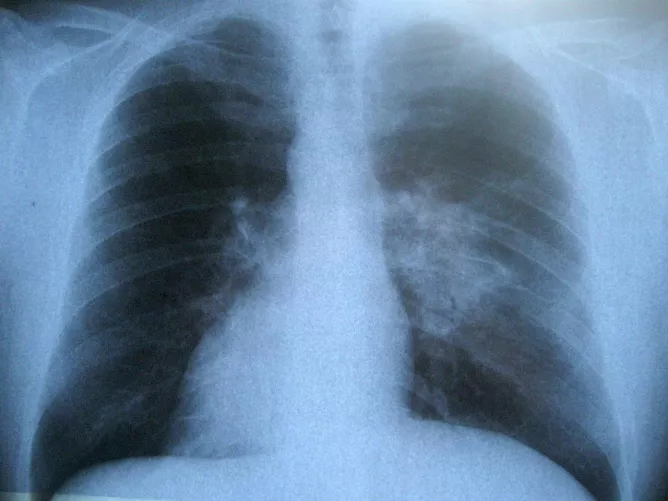

Ha a tüdőt is megtámadja a betegség, hegesedés és gyulladás alakul ki a léghólyagokban, a tüdő merevvé válik és sokat veszít a kapacitásából. A betegnél nehézlégzés, rendszeres száraz köhögés alakul ki.

A szisztémás szklerodermában szenvedő betegeknél a leggyakoribb halálok a tüdő nagyfokú érintettsége, ezért az egyik legfontosabb vizsgálat a szklerodermával kapcsolatban erre a szervre terjed ki. Először légzésfunkciós vizsgálattal, ha pedig szükséges, nagy felbontású CT-vel deríthető ki a betegség fennállása. Autoimmun betegség lévén, az alapkezelés immunszupresszív, azaz az immunrendszert befolyásoló beavatkozás, melyet kiegészíthetnek különböző más kezelések is, szervi érintettségtől függően.